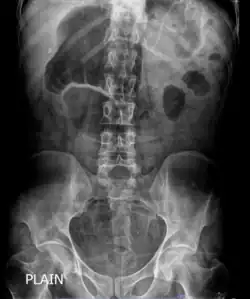

X-ray showing distended stomach and bowel loops. Dilated bowel loops are a characteristic of chronic intestinal pseudo-obstruction. | |

In order to look into possible intestinal obstruction, radiologic examinations are essential. Simple and cheap to perform, plain film x-rays can show the traditional indicator of air-fluid levels and dilated bowel loops, which is best seen in the erect film.[25] Abdominal x-rays, however, are unable to definitively differentiate between genuine mechanical intestinal obstruction and pseudo-obstruction.[26] Afterwards, additional information is obtained by abdominal computed tomography (CT) imaging in order to rule out an extraluminal, gut wall, or intraluminal mechanically obstructive lesion.[25]